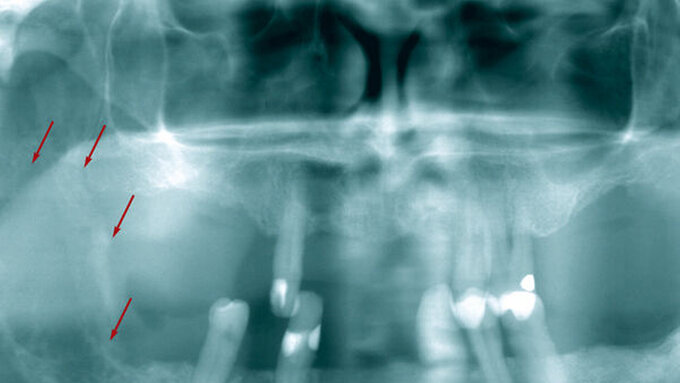

Eine 32-jährige Patientin stellte sich mit Parästhesien im linken Unterkieferbereich in einer oralchirurgischen Praxis in Foggia (Italien) vor. Sie berichtete, dass die Beschwerden seit fünf Tagen bestanden und sie vor drei Jahren eine radikale Bimastektomie wegen eines invasiven lobulären Mammakarzinoms hatte. Sie erhielt Chemotherapie und Bestrahlung sowie eine Dauertherapie mit 4 mg Zoledronsäure intravenös alle drei Wochen. Intraorale zeigte sich eine gute Mundhygiene, keine Schwellungen, Fisteln oder offene Schleimhaut. Auffällig waren allerdings regionale Lymphknotenschwellungen submandibulär sowie eine von extraoral tastbare, leichte Schwellung im Bereich des Kieferwinkels linksseitig. Es wurden ein PET-CT sowie ein DVT angefertigt.

In der sagittalen Ebene des DVTs zeigte sich „eine kleine, wenig diffuse Röntgenopazität in der Nähe des Unterkieferwinkels sowohl auf der medialen als auch auf der lateralen Fläche […]. Die PET-Ergebnisse zeigten eine Fluor-2-Desoxy-D-Glucose-Aufnahme im linken Winkelbereich des Unterkiefers.“ Es wurde im Anschluss eine Feinnadelaspirationszytologie durchgeführt, die Merkmale eines metastasierenden Mammakarzinoms ergab. Differenzialdiagnostisch kam hier auch eine Osteonekrose aufgrund der Bisphosphonatbehandlung in Frage. Die Patientin wurde zurück an ihren Onkologen verwiesen.